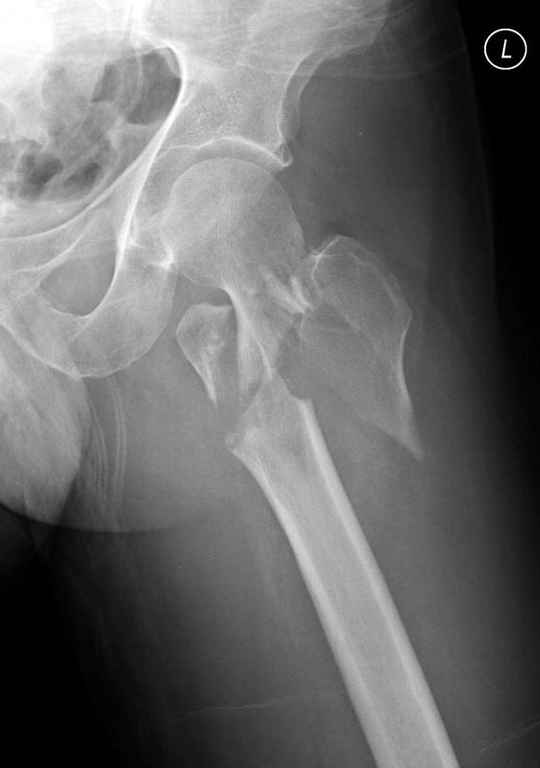

А что тут заставляет сомневаться? Здесь настолько очевидно предпочтителен закрытый интрамедуллярный остеосинтез реконструкционным стержнем (проксимальные гвозди толстоваты для такого молодого возраста), что закрадывается мысь о каком-то подвохе.

Желательно бы и снимок бедра на протяжении и в другой проекции.

Не солидно экономить на пленке, это не делает чести презентации. Такие ограниченные нестандартные снимки приводят к тактическим ошибкам.

Предугадать распространение линий перелома при чрезвертельных и оскольчатых переломах трудно, поэтому для принятия правильного решения рекомендуется Компьютерно Томографические исследование.

При отсутствии КТ, снимок на вытяжении поможет увидеть общую картину расположения отломков, особенно потенциальные места введения импланта. Риск раскола в этом случае огромный, поэтому больной должен быть дообследован.

А так для лечения оскольчатых переломов подходят все методы, включая интра- и экстрамедуллярные в зависимости от опыта и наличия импланта.

Здесь пара похожих случаев.